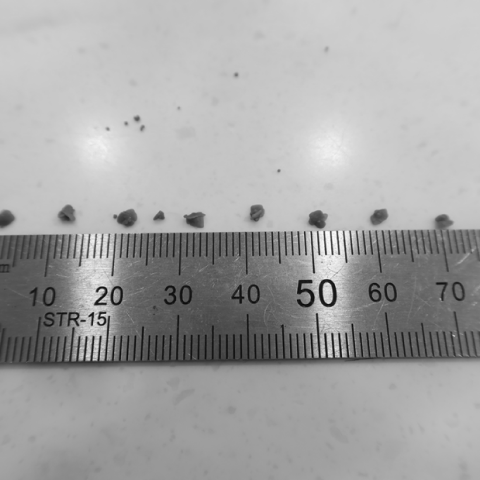

‘VUH’를 이용해 수술 없이 꺼낸 결석들